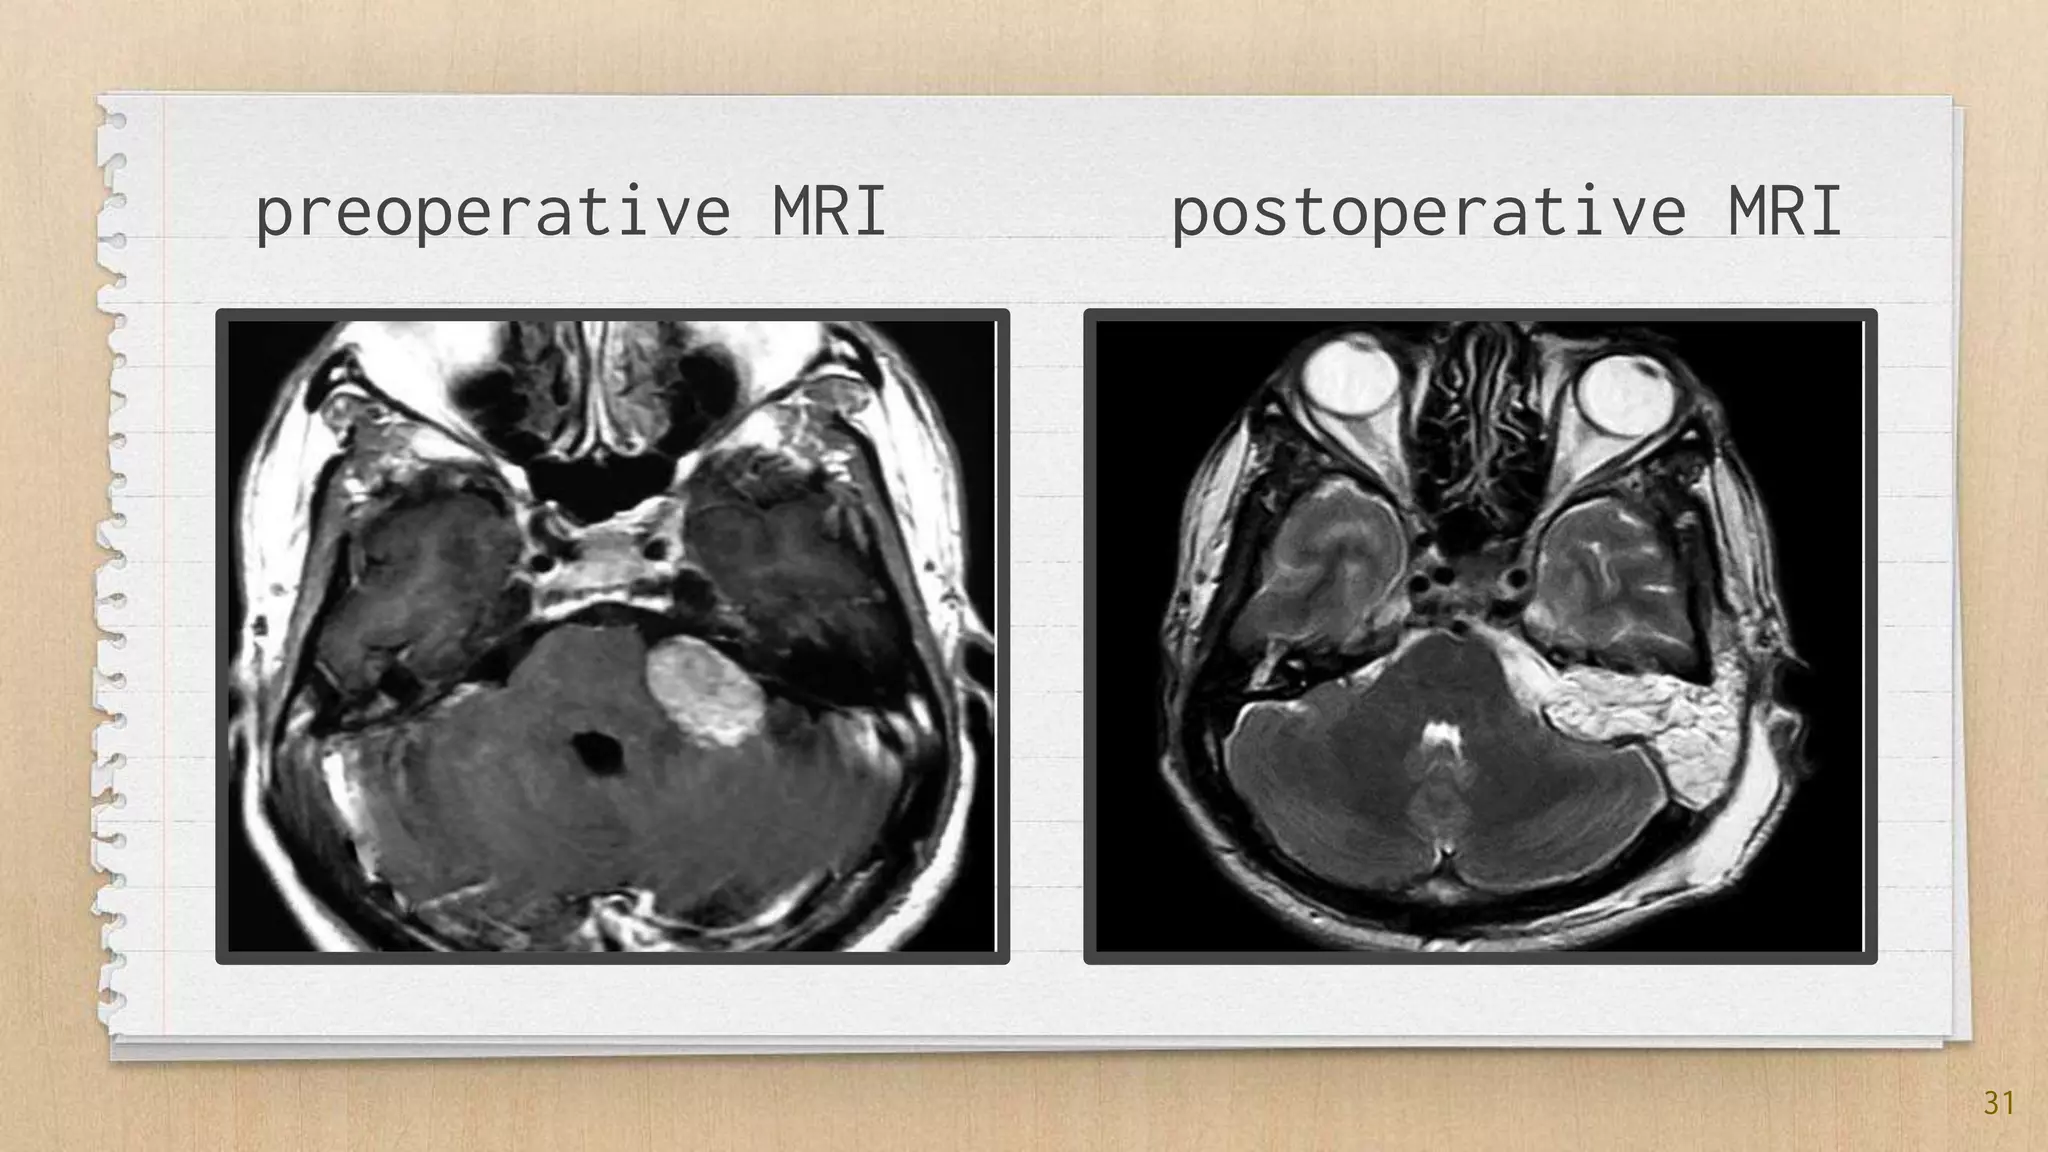

Vestibular schwannoma (acoustic neuroma) surgical anatomy and ...